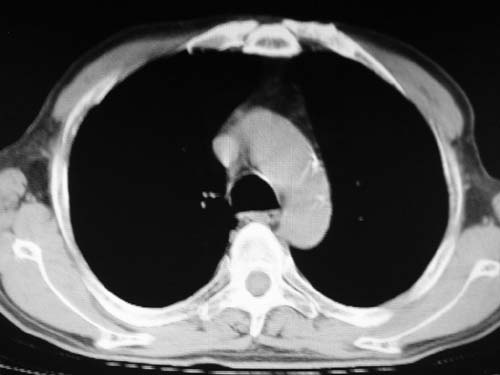

左下肺静脉扩张,原因?建议cta

结合患者年龄,不除外左下肺扩张性动脉瘤,建议胸透是否有扩张性博动,以便确诊。

右肺上叶尖段结核;左肺下叶占位?建议增强扫描。右侧胸膜增厚;右肺局限性肺气肿。